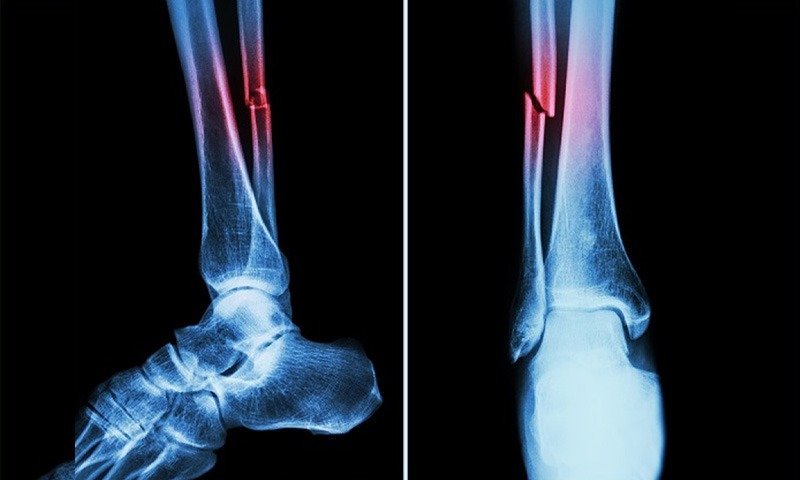

طبی دنیا میں انقلاب، منٹوں میں فریکچر جوڑنے والا سپر گلو تیار

چین کے محققین نے ہڈیوں کے فریکچر کو منٹوں میں جوڑنے والا انقلابی سپر گلو تیار کر لیا ہے، جو روایتی طور پر کئی ماہ کے بعد جوڑنے والی ہڈیوں کے علاج کو چند منٹوں میں ممکن بنا دیتا ہے۔ چین کی ژے جیانگ یونیورسٹی کے ماہرین نے اس سپر گلو کو بون-2 کا نام…